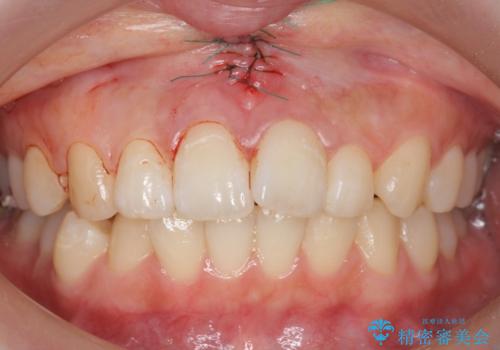

上唇小帯切除

矯正を行なっても後戻りのリスクが高いので、上唇小帯の切除を行いました。

- 外科手術のため、術後に出血、痛みや腫れ、違和感を伴います